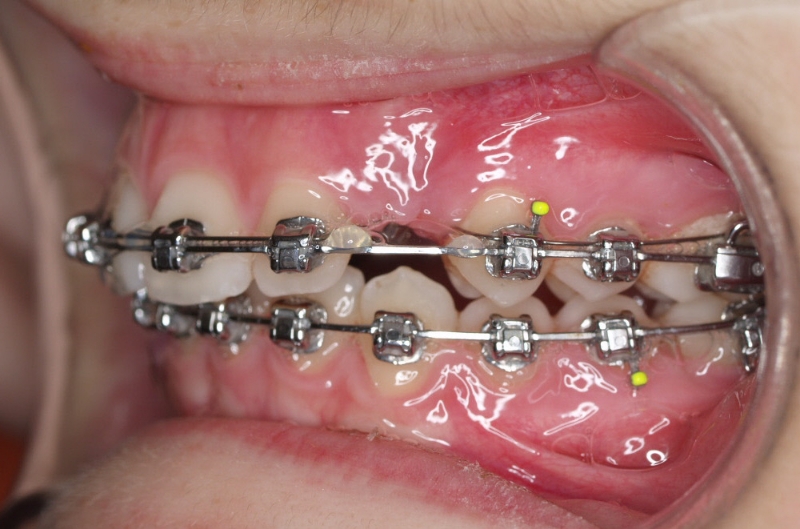

Clase II paciente 15 años

La paciente O.O. acude a nuestra consulta por:

– Canino 13 e incisivo lateral 42 en posición ectópica.

– Canino 23 incluido.

Con lo que decide realizarse un tratamiento de ortodoncia de duración de 24 meses con brackets damon Q.

CASO COMPLETO: